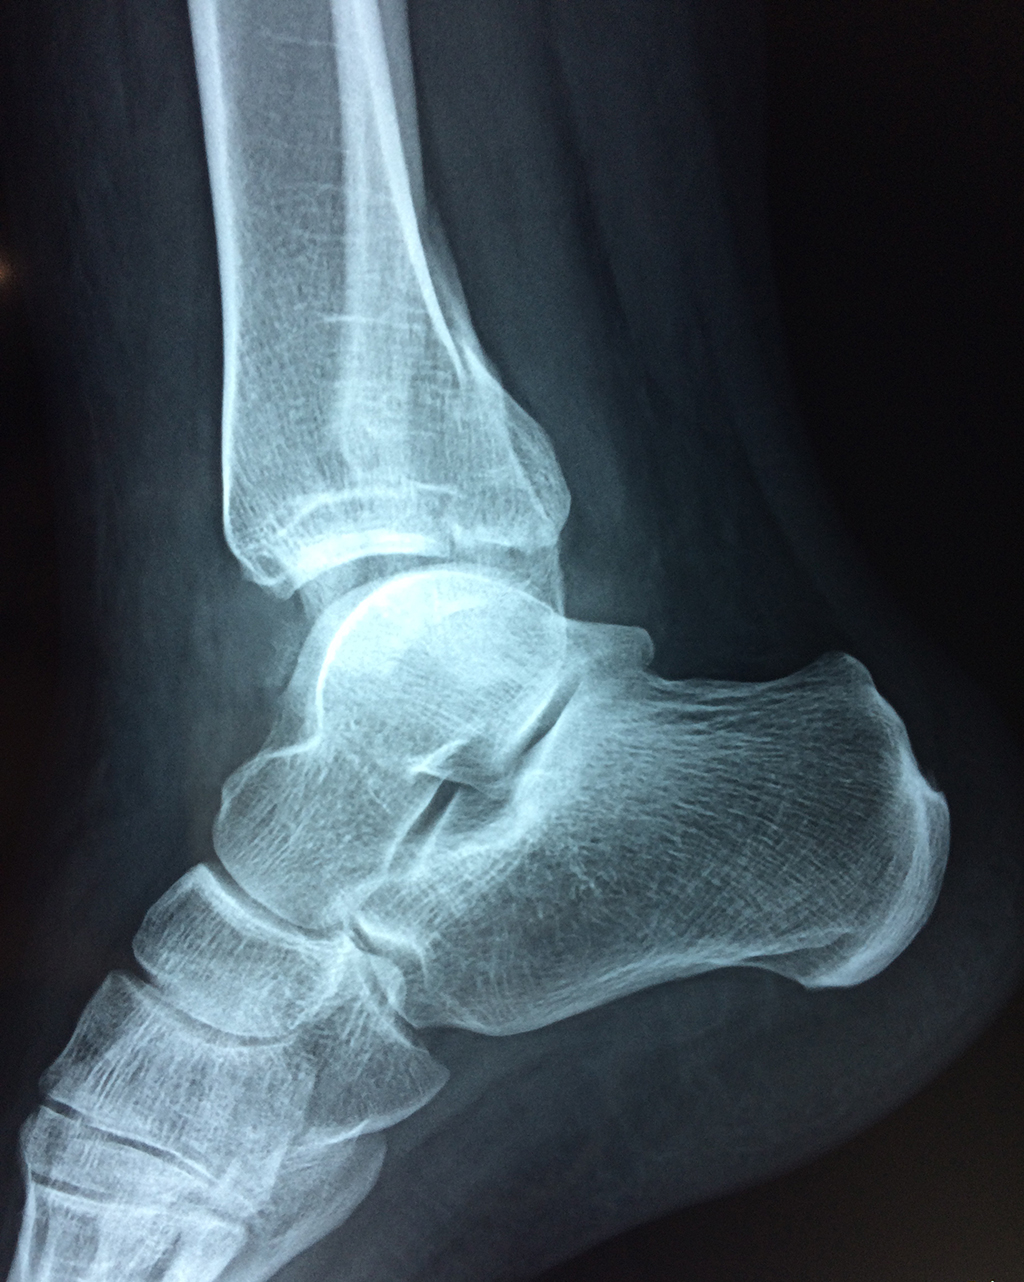

Una fractura de tobillo es la rotura de uno o más de los huesos del tobillo. Estas fracturas pueden ser:

- Parciales (el hueso está sólo parcialmente fisurado, no del todo).

- Completas (el hueso está perforado y está en 2 partes).

- Producirse en uno o ambos lados del tobillo.

Algunas fracturas de tobillo pueden requerir cirugía si:

- Los extremos de los huesos están desalineados entre sí (desplazados).

- La fractura se extiende hasta la articulación del tobillo (fractura intra-articular).

- Los tendones o ligamentos (tejidos que sujetan los músculos y los huesos entre sí) están rotos.

- El médico cree que sus huesos probablemente no sanen apropiadamente sin cirugía.

- El médico considera que la cirugía puede permitirle una recuperación más rápida y confiable.

- En los niños, la fractura involucra la parte del hueso del tobillo donde el hueso está creciendo.

Cuando se necesita cirugía, es probable que esta implique el uso de clavijas de metal, tornillos o placas para sostener los huesos en su lugar mientras la fractura se consolida. Los elementos de soporte pueden ser temporales o permanentes.